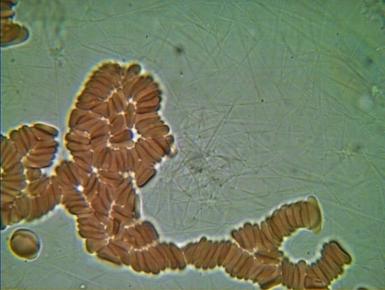

1.RULONIZACJA I AGREGACJA ERYTROCYTÓW

To poważne zagrożenie zatorowo - zakrzepowe, co klinicznie może spowodować zapalenie naczyń obwodowych, zawał serca, udar mózgu a nawet nagły zgon. Agregacji i rulonizacji nie można stwierdzić tradycyjnymi badaniami diagnostycznymi.